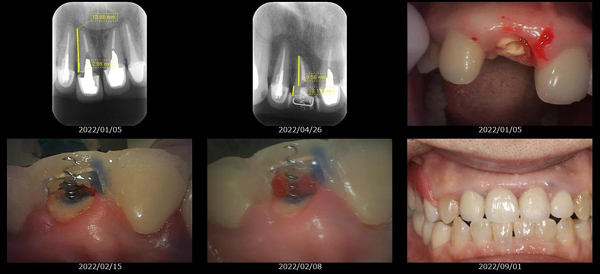

救歯MTM

虫歯が大きくて残せない歯、転倒などの事故により歯が根の深いとこで折れてしまったなどで、抜かざるを得ない歯を、骨の中に埋まっている健全な根を、骨の上に矯正的に引き上げることで、その歯を抜かず温存、救歯できる可能性のある治療方法です。

この特別な診療である救歯MTMは、以下のような特徴があります。

①健全な歯を、歯肉から見える位置にまで引き上げることで

根の治療の成功率を上げることが出来る。唾液には沢山の細菌がいます。唾液が入らない環境での根の治療を(神経の治療)を行うことで神経の治療、根の治療の成功率は格段と上がります。

②骨の上にある歯と土台で支える被せもの製作できる。

被せものを土台だけに頼ることなく、引き上げた健全な歯でも支えることで、歯への被せ物がしっかりと装着できるようになる。

③抜かずに歯を活かすことで、隣の歯を削るブリッジやインプラントにしないで済むことがある。

歯を矯正的に引き上げることで、その歯を救歯できるだけでなく、隣の歯を削るなどの侵襲を回避できる場合がある。

救歯治療と審美性の両立

当院では様々な治療の基礎に審美と機能の両立というテーマがあります。

リスク

- > 歯を矯正的に引き上げることで、骨の中の根の長さは短くなりますが、その短さでも安定するという診断をした場合のみ施術になります。 残せる歯、根の長さが短い場合は、この救歯MTMの治療対象とならない場合がございます。

- > 治療期間が数か月~1年に及ぶ場合がある。

- > 費用が自費診療 44,000円 ~ 66,000円

- > 救歯MTMは救歯BTAセラミックと併用治療が必要な場合があります。

症例